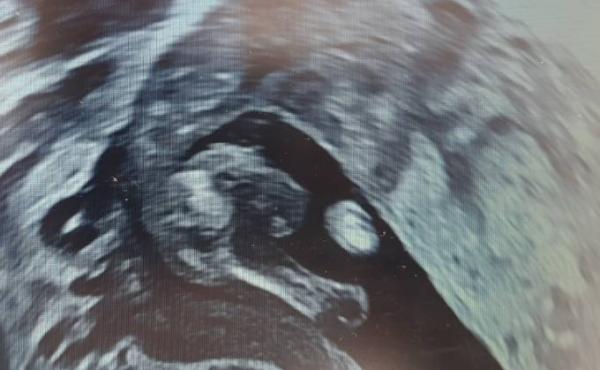

Hier nun noch das Outing  Aber vielleicht erkennt ihr ja etwas anderes?

Aber vielleicht erkennt ihr ja etwas anderes?

Ich sehe da sehr eindeutig alles, was zu einem Jungen gehört. Da ich gerade eben erst ein eindeutiges MĂ€dchen im US gesehen habe, umso mehr. Hihi, herzlichen GlĂŒckwunsch!

Also ich muss auch sagen, dass das Bildchen doch recht eindeutig aussieht.

und ich finde auch voll eindeutig ein Junge.